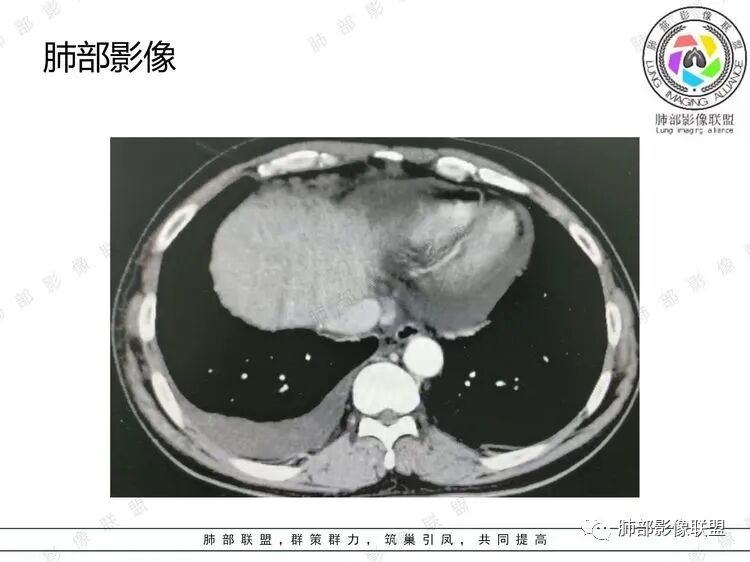

B超:腹膜后淋巴结肿大。胸部CT:纵隔、右肺门多发肿大淋巴结,部分融合呈团块状,纵隔淋巴结有坏死,右肺多发中轴间质增厚及小叶间隔增厚,部分实变,沿支气管血管束分布有多发粟粒结节影,右侧胸腔积液,心包积液。

积液可能是低蛋白血症 心衰

6.心包积液,心包未见强化结节影。

7.肝脾未见增大。